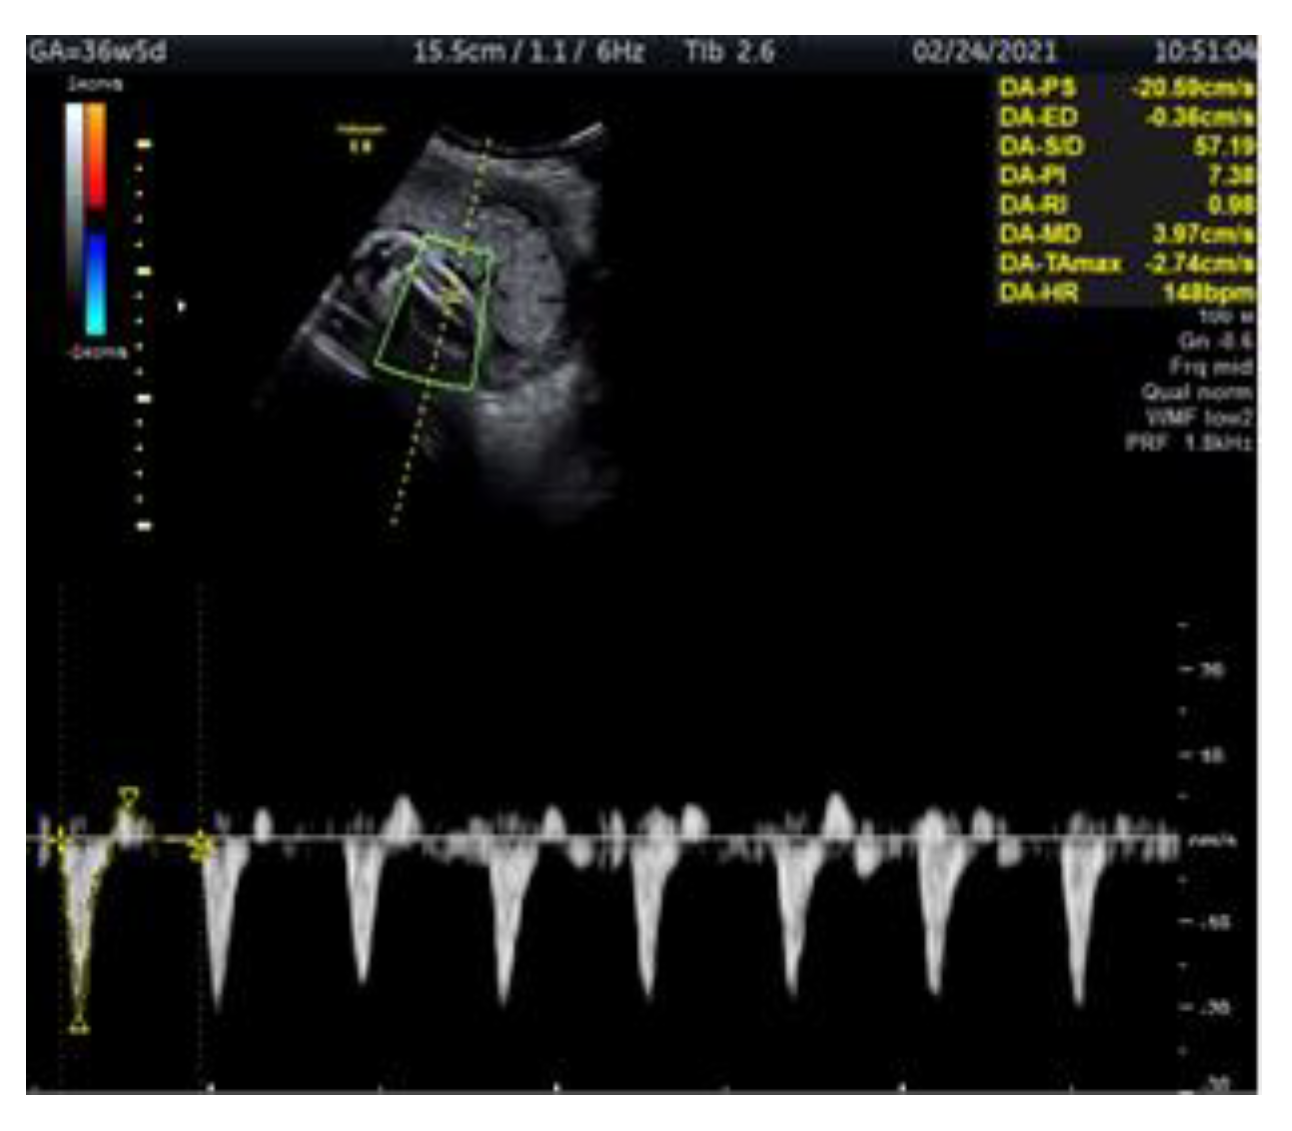

Doppler Ultrasonography of the Fetal Tibial Artery in High-Risk Pregnancy and Its Value in Predicting and Monitoring Fetal Hypoxia in IUGR Fetuses

2. Case Report